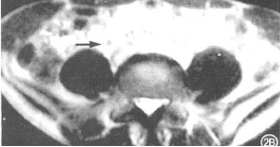

T2WI 见高信号管腔内低信号结节(箭头处)

MRI或MRU:T1WI平扫为等信号结T2WI输尿管内液体高信号,息肉呈低信号;增强轻度强化明确检查,最终依靠输尿管镜检查+活组织病理。可明确病变部位、数目及性质;镜下可见息肉呈灰白色,表面光滑,可在输尿管内漂移,有蒂;术中可取活检进一步明确诊断,对指导手术有决定意义;对于IVP或逆行尿路造影提示有输尿管梗阻而原因未明者,早期应用输尿管镜行输尿管探查,可进一步明确。